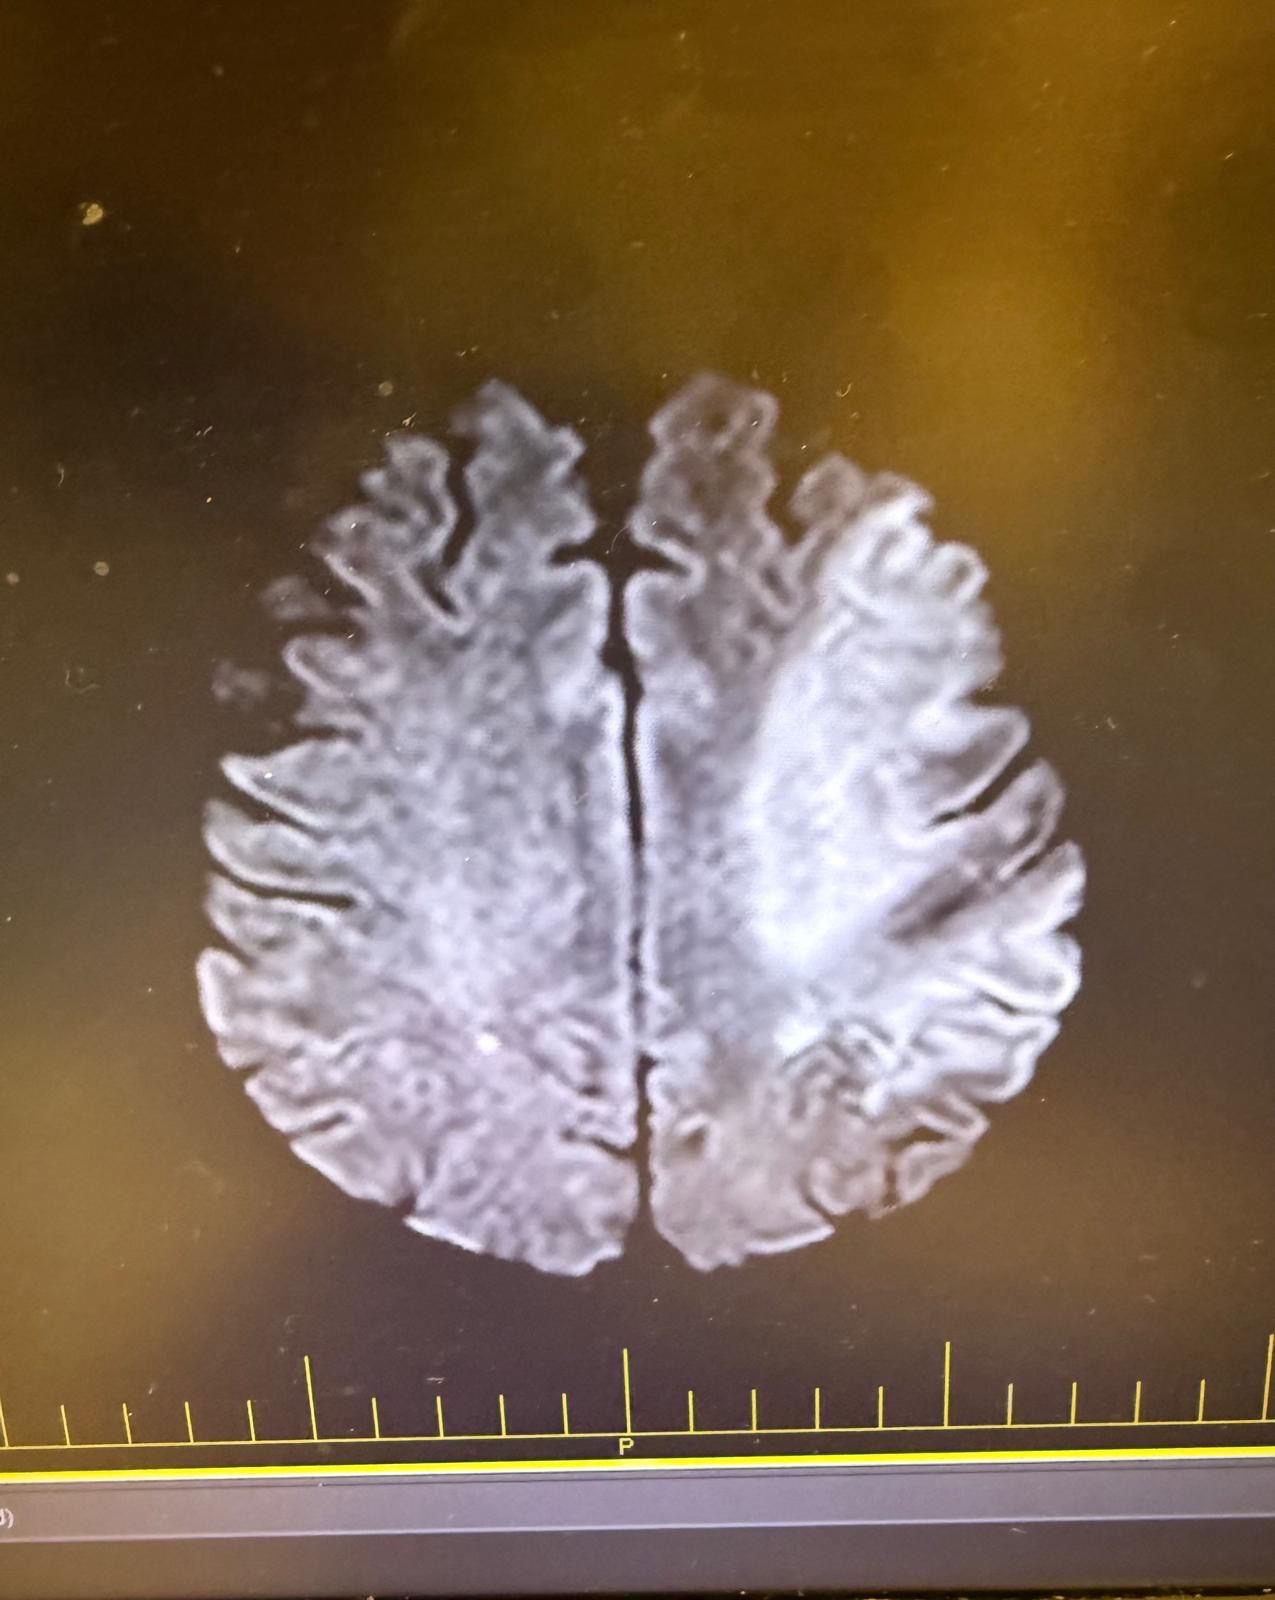

Our mom recently suffered multiple strokes but did not receive any medical care until her second stroke. She blamed her initial stroke symptoms on something else and didn’t want to get checked out due to lack of insurance. It wasn’t until the second stroke, after a whole day of symptoms, that she was finally taken to the emergency room.

She is now bedridden and unable to speak due to the strokes. She has zero mobility on her right side because of where the stroke was. It was devastating to see my mother in such a state. But we see her in there. Our mother understands everything we say and she shows us that she could get better little by little. The doctors say she’ll never be how she once was, but she shows willingness to get better, and today she showed signs of physical affection.